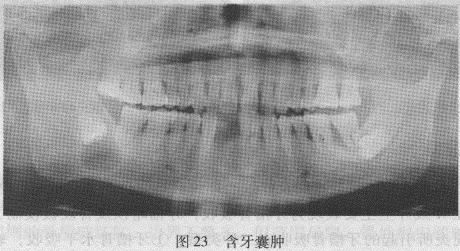

【答案】1.根尖囊肿(见根尖周炎)。2.含牙囊肿又称滤泡囊肿,属颌骨发育性囊肿,发生在牙齿形成过程的早期,X线特点是囊肿内含有各个发育不同阶段的牙(恒牙多见),牙冠一般朝向囊腔,囊壁通常连于冠与根交界外,单房多见,多房少见(图23)。

2.含牙囊肿又称滤泡囊肿,属颌骨发育性囊肿,发生在牙齿形成过程的早期,X线特点是囊肿内含有各个发育不同阶段的牙(恒牙多见),牙冠一般朝向囊腔,囊壁通常连于冠与根交界外,单房多见,多房少见。